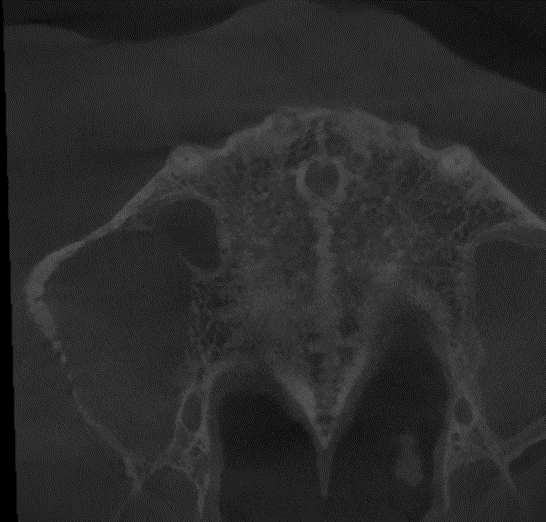

En la TCHC se observó una zona mixta multilocular en el trabeculado óseo, de límites mal definidos y no corticalizados, de forma irregular, con perforación de las tablas óseas vestibular y palatina. Además, se evidenció el seno maxilar derecho con marcado engrosamiento de la mucosa sinusal y la cortical sinusal parcialmente perforada (Figura 2). El estudio histopatológico denotó pequeñas células linfoides, lo que, en conjunto con la TCHC, sugiere un diagnóstico presuntivo de Linfoma No Hodgkin.

Figura 2. Reconstrucción panorámica de TCHC (A), corte axial (B) y corte transversal (C).